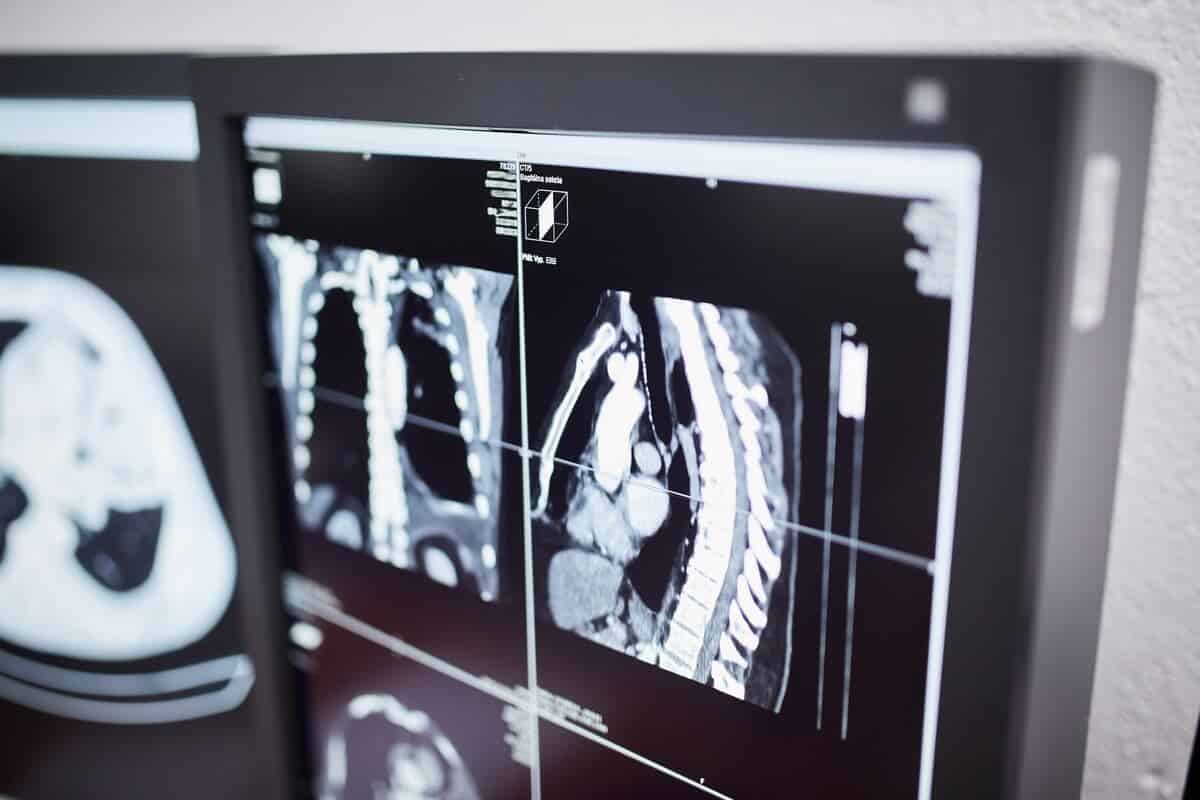

• Vyšetrenia počítačovou tomografiou (CT)

Rádiodiagnostické pracovisko je vybavené zobrazovacou technikou, ktorá umožní vykonávať na pracovisku komplexnú škálu zobrazovacích vyšetrení.

• vyšetrenia počítačovou tomografiou (CT),

CT pracovisko (počítačová tomografia)

VYŠETRENIA:

• CT mozgu, perfúzne CT mozgu

• CT angiografia extra a intrakraniálnych ciev

• CT krčnej, hrudnej a bedrovej chrbtice

• CT hrudníka

• HRCT pľúc

• CT angiografia pulmonálnych artérií

• CT krku

• CT kĺbov a kostí

• CT chrbtice

• CT brucha a malej panvy

• CT pečene- fázované

• CT hrubého čreva – CT irigografia a virtuálna CT kolonoskopia

• CT tenkého čreva – CT enterografia

• CT angiografia brušnej aorty a viscerálnych artérií

• CT obličiek

• CT angiografia renálnych a končatinových artérií

• CT flebografia

• Periradikulárna terapia a ozonoterapia pod CT (v spoluprácii s neurologickým oddelením nemocnice)